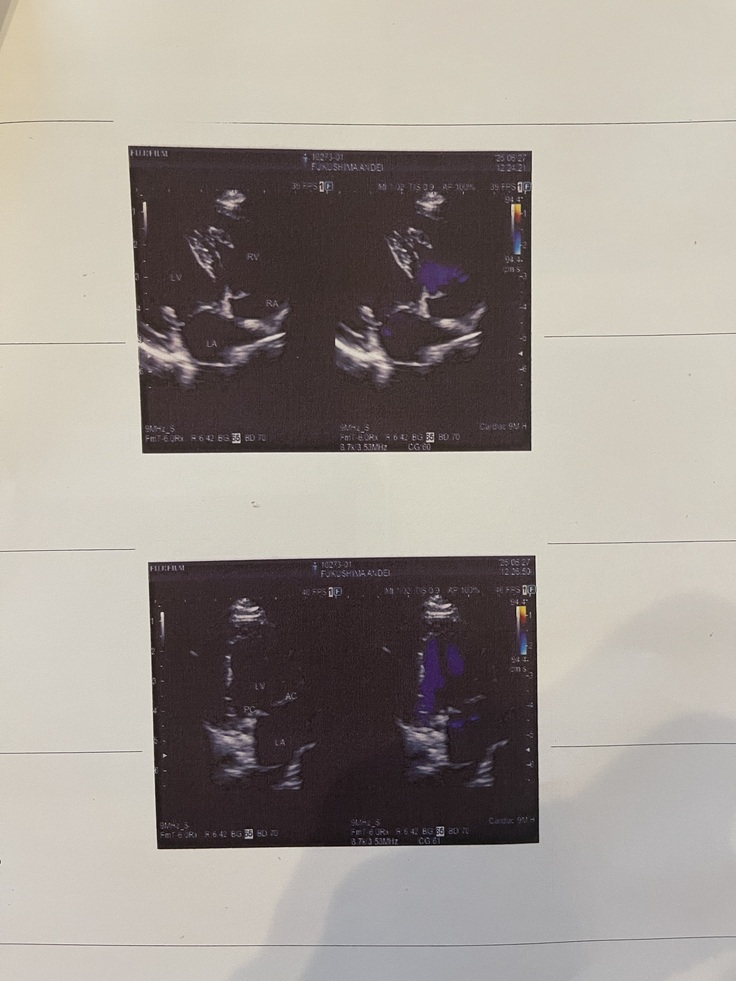

術後3か月検診に行ってきました🐶

6月27日に検診に行ってきました🐶🏥

結果は、『完治とみて良い』とのことでした✨✨✨✨

心臓の治療は3か月検診をもって終了となりました👏㊗️

なので、1日2回服用していた強心剤も終了です💊

3か月以降に術後の合併症が出てくることもほぼ無いそうです🐶

三尖弁はわずかに逆流はありますが、経過観察です。